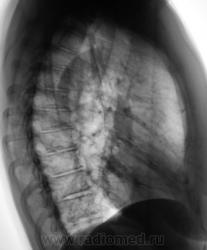

Мой дифф ряд:

c-r ателектаз язычковых сегментов/массивные шварты. Справа по-моему это "ничего". Игра теней. Хотя на пленке картинка, возможно, несколько иная. Скопия очень помогла бы.

Отличить шварты и ателектаз.